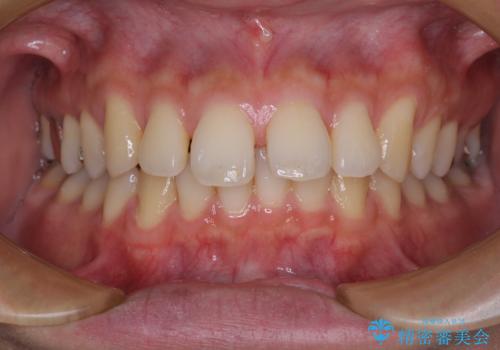

深い咬み合わせと前歯の隙間 ハーフリンガルによる矯正治療

- 咬み合わせにより上顎正中に隙間ができているとのことで来院された患者様です。

インビザラインは自己管理が煩わしく、表側のワイヤー装置は目立つので避けたいとのことで、上顎だけが裏側装置のハーフリンガルにて矯正治療を行うこととしました。